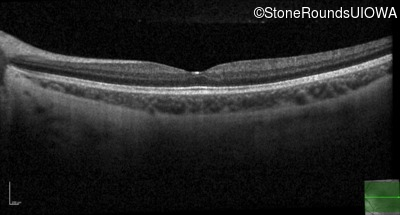

XL Retinoschisis (IIIB1)

XL Retinoschisis (IIIB1)

This 6 year old boy first experienced difficulty reading and seeing the blackboard at age 5.

| XL Retinoschisis | RS1 | Pro192His CCC>CAC | XL |